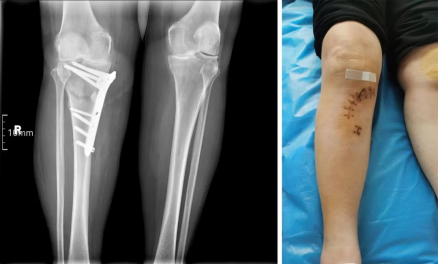

(术前X线)入院后,贵州医科大学第三附属医院骨科副主任、副主任医师王栋为崔奶奶进行了详细查体和检查,发现崔奶奶右膝关节明显内翻畸形,外侧软骨和半月板功能正常,比较适合行右侧胫骨近端高位截骨术。在与崔奶奶及家属沟通后,决定实施该手术,为她保住膝盖。 术前,贵医附院骨科主任医师、博士后叶川与贵州医科大学第三附属医院骨科团队一起,展开了科学而全面地评估及讨论,借助计算机软件,围绕切口、暴露部位、股骨截骨线和截骨量等,制定了详细精确的术前规划。手术当天,过程十分顺利,创伤较小,出血量少。术后,崔奶奶恢复了右下肢正常的生物力线。通过手术,她的右膝畸形不仅得到了矫正,而且膝关节的稳定性和活动度也得到了最大程度的保留。右膝屈伸活动基本不受限制,疼痛也明显缓解,崔奶奶及家属都很满意。术后情况